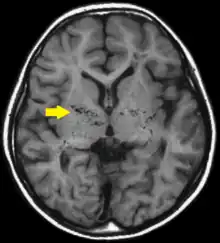

| T1-weighted MR image of moyamoya disease. Flow void in the basal ganglia is indicated by the arrow. | |